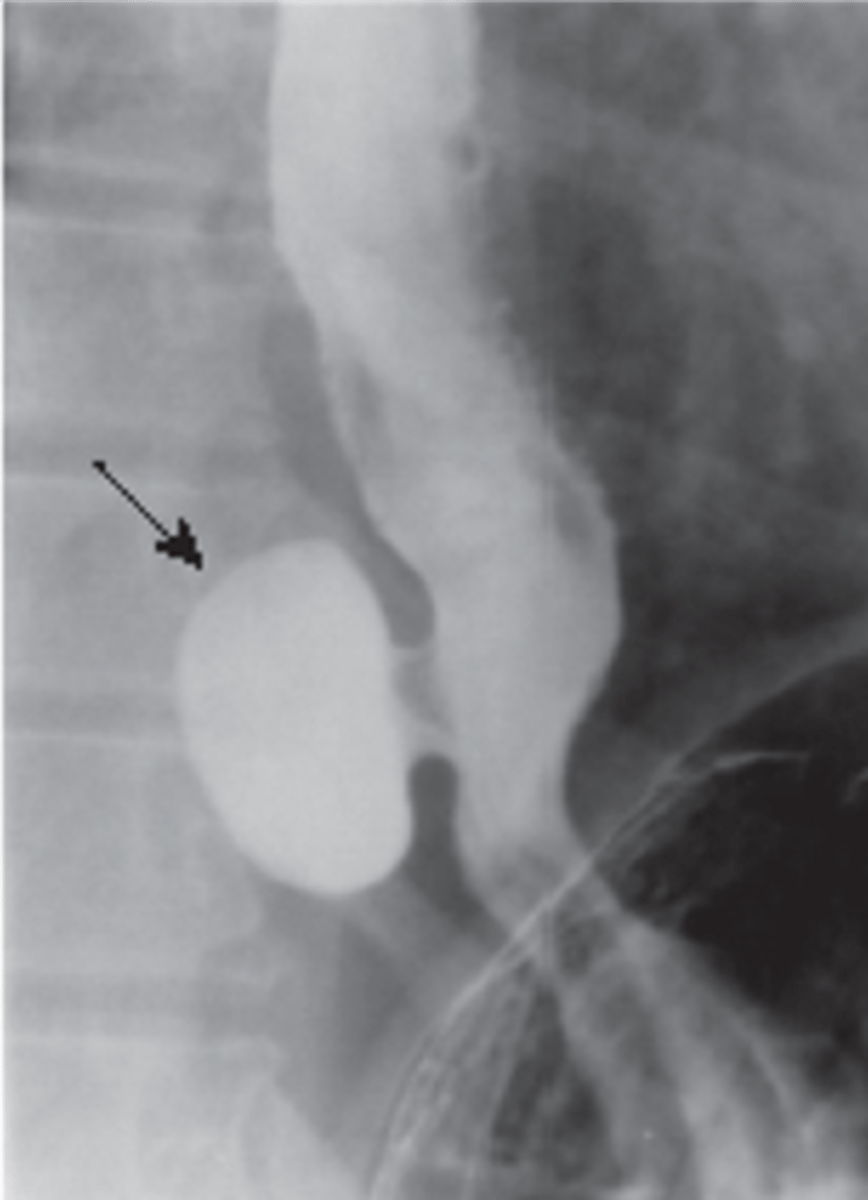

Zenker's diverticulum